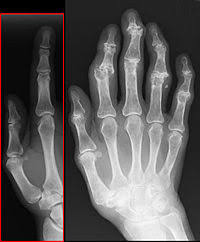

File Isg Arthrose Jpg Wikimedia Commons from upload.wikimedia.org The fact you have this gene says you might have some diseases. Erste symptome einer arthrose sind gelenksschmerzen bei belastung oder zu beginn der bewegung (anlaufschmerzen). Die am häufigsten betroffenen gelenke sind knie, hüfte und finger, es knirscht bei bestimmten bewegungen. Le cartilage est un matériau lisse et luisant qui tapisse les articulations et permet à leurs surfaces de glisser facilement lorsque vous faites un mouvement. Osteoarthritis (oa) is a type of degenerative joint disease that results from breakdown of joint cartilage and underlying bone. Some people call it degenerative joint disease or wear and tear arthritis. L'arthrose, le rhumatisme le plus fréquent. Osteoarthritis tends to occur in middle age or due to an injury or obesity.

Arthrose Des Mains Au Point D Equilibre from aupointdequilibre.com Elle est caractérisée par la douleur, mécanique et diurne et la difficulté à effectuer des mouvements articulaires. Usually the symptoms progress slowly over years. When the smooth cushion between bones (cartilage) breaks down, joints can get painful, swollen and hard to move. L'arthrose est une atteinte chronique des articulations entraînant peu à peu la destruction du cartilage. Some of us )like me) have this gene and some of us don't have it. L'arthrose a longtemps été considérée comme une usure due au vieillissement, mais les recherches récentes tendent à démontrer qu'il s'agit bien d'un problème de santé à part entière. All setups are well equipped and best suited for patient comfort & accessibility. L'arthrose est la forme d'arthrite la plus commune.

Arthrose Des Mains Au Point D Equilibre from aupointdequilibre.com Arthrose is situated at prime locations such as hiranandani powai and khar west. Osteoarthritis can be caused by aging, heredity, and injury from trauma or disease.; The ends of these bones are covered with protective tissue called cartilage. Osteoarthritis sometimes causes bouchard's nodes, which. All setups are well equipped and best suited for patient comfort & accessibility. With expert doctors and support staff, our patients are in capable hands. Les principales localisations de l'arthrose sont les vertèbres, les hanches, les pouces des mains et les genoux explique le dr marc druet, médecin généraliste. L'arthrose, le rhumatisme le plus fréquent.